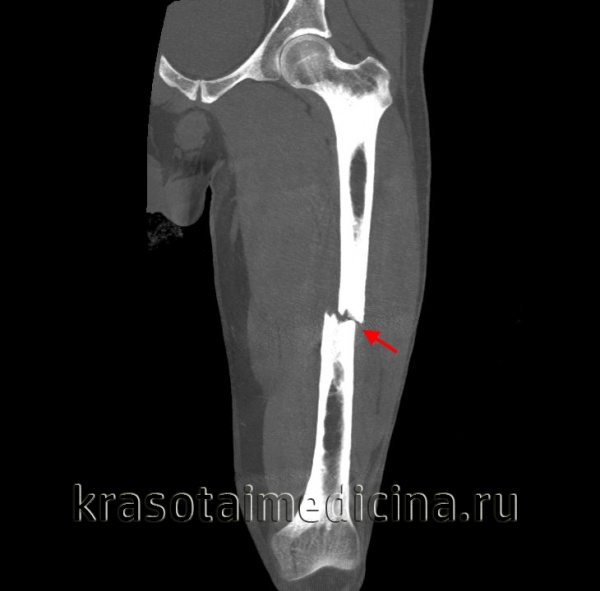

Перелом бедра ( Перелом бедренной кости )

Переломы бедра составляют около 6% от числа всех переломов костей. Выделяют три основные группы переломов бедра: переломы верхнего конца бедра, диафизарные переломы и переломы нижнего конца бедра. В зависимости от места перелома бедра он может проявляться болью, ограничением подвижности бедра, укорочением и деформацией поврежденной конечности. При открытом переломе возможна значительная кровопотеря. Основной способ диагностики переломов бедра - это рентгенография. При внутрисуставных переломах бедра дополнительно проводится МРТ сустава. Лечение перелома бедра заключается в репозиции отломков и их фиксации спицами, трехлопастным гвоздем или аппаратом внешней фиксации; по показаниям применяется скелетное вытяжение.

Переломы тела бедренной кости

Диафизарный перелом бедра – тяжелая травма, сопровождающаяся болевым шоком и значительной кровопотерей.

При прямой травме возникают поперечные, косые и оскольчатые переломы бедра, при непрямой – винтообразные. При переломе бедра на отломки воздействует большое количество мышц, прикрепляющихся к бедренной кости. Мышцы тянут отломки в стороны, вызывая их смещение. Направление смещения зависит от уровня перелома.

Пациент с переломом бедра предъявляет жалобы на сильную боль в месте повреждения. В области перелома наблюдается отечность, кровоизлияние, деформация конечности и патологическая подвижность. Нога, как правило, укорочена. Перелом бедра может сопровождаться повреждением нерва или крупного сосуда. Возможно развитие травматического шока, обусловленного резкой болью и выраженной кровопотерей.